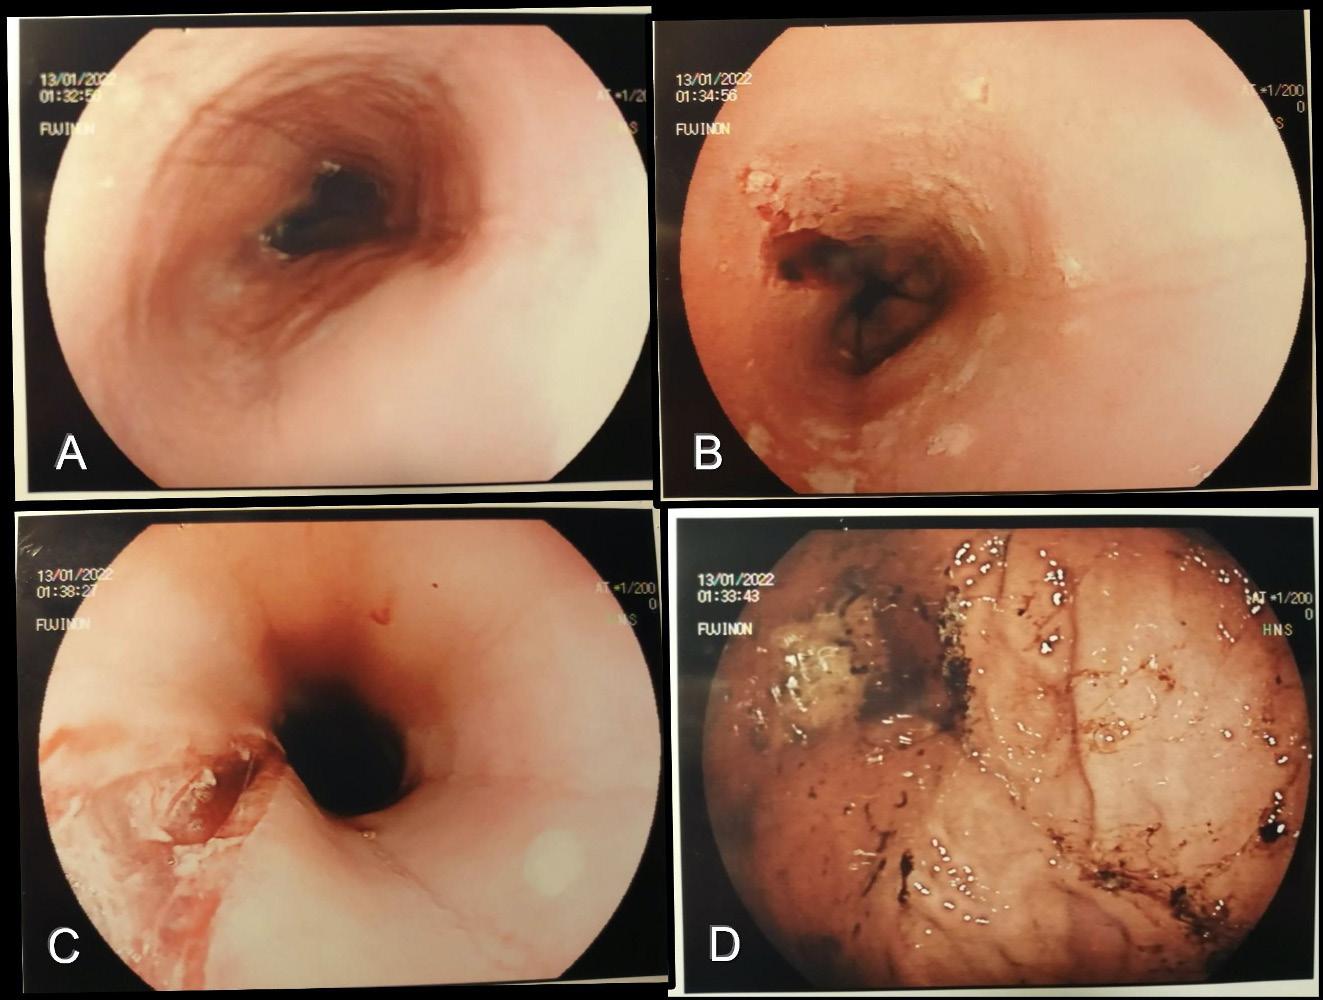

1.

in un caso

scopico può essere molto suggestivo con immagini di “esofago trachealizzato”, striature longitudinali o lineari (80%), anelli mucosali (64%), riduzione di calibro del lume (28%), placche e/o essudato (16%), stenosi (12%) [Figura 1]. Lo score EREFS (Eosinophilic Esophagitis Endoscopic Reference Score) considera 5 aspetti principali della mucosa – edema, anelli, essudato, solchi e stenosi – e consente di dare uniformità alla descrizione dei reperti facilitando la diagnosi differenziale tra EoE e altre patologie esofagee [Figura 2; Tabella 2]. In un terzo dei casi l’aspetto macroscopico della mucosa è normale ed è quindi fondamentale effettuare comunque le biopsie che devono essere multiple (da due a quattro) e prelevate a più livelli dell’esofago (prossimale e distale). Il corretto campionamento include anche biopsie gastriche e duodenali. L’eosinofilia non è esclusiva dell’EoE e, per la diagnosi differenziale, le linee guida dell’ESPGHAN indicano i criteri corretti: l’infiltrato eosinofilo deve essere denso ma irregolare, usualmente associato a microascessi o degranulazione cellulare e la conta cellulare deve essere ≥ 15 eosinofili/per campo ad alto ingrandimento (hpf). La relazione tra MRGE ed EoE resta controversa: le due patologie potrebbero semplicemente sovrapporsi, l’EoE potrebbe favorire la MRGE per una inadeguata peristalsi esofagea o la MRGE potrebbe concorrere alla patogenesi dell’EoE erodendo l’epitelio e aumentando il rischio di sensibilizzazione alimentare. Non sempre le indagini pH-impedenzometriche valgono a discriminare le due patologie. Oltre a questo, l’esofagite eosinofila responsiva a inibitori di pompa protonica (PPI-responsive eosinophilic esophagitis) è tipica di un sottogruppo distinto di pazienti che presenta caratteristiche cliniche e istologiche suggestive di EoE ma che ha, al contempo, una

Figura

Esofagoscopia

di EoE. Anelli circonferenziali (A), lacerazione della mucosa (B,C) e multiple erosioni a fondo fibrinoso (D). (da Fernicola et al. Quaderni acp 2022;29:177-9).